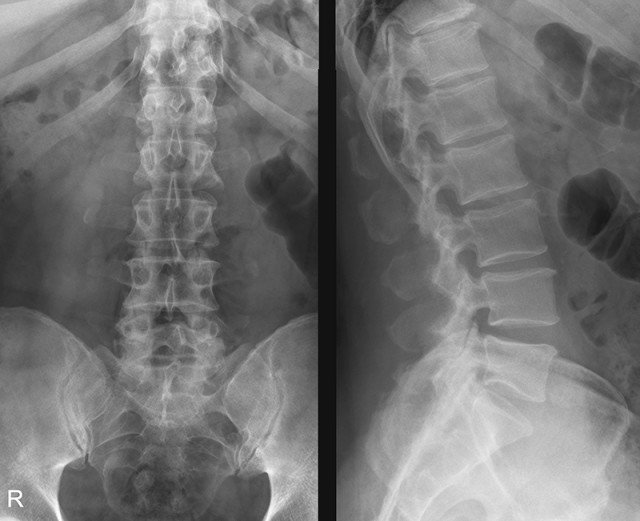

Прежде всего, стоит назвать его основное отличие от рентгеноскопии. Наука не стоит на месте, в том числе и медицинская, старые технологии устаревают, а на смену им приходят новые. Проблема в том, что рентген, как метод диагностики, давно и безнадежно устарел. Он используется по инерции, «по старинке» и совершенно не показывает таких результатов как УЗИ, притом, что вреда от рентгена (хоть и опосредованно) может быть больше.

Рентген как метод обследования устарел и уступает УЗ-диагностике

Кстати. При прохождении рентгенологического исследования пациент помещается между фотопленкой, на которой проецируется изображение, и источником излучения, проводящим волны сквозь человеческое тело.

В результате рентгена образуется черно-белая картинка, которая позволяет увидеть довольно мелкую детализацию, но радиационное облучение при этом попадает прямо в человеческий организм. И доза его варьируется в зависимости от того, какой по площади участок тела необходимо диагностировать. Позвоночник обычно занимает большую площадь, поскольку редко исследуется одна его зона, обычно облучению подвергаются как минимум две (например, шейно-грудная или пояснично-крестцовая). Поэтому рентген нельзя делать беременным и тем, кто кормит грудью, а также имеющим почечную недостаточность пациентам. Способ с применением ультразвука не имеет таких противопоказаний и ограничений.

Противопоказания к рентгенографии